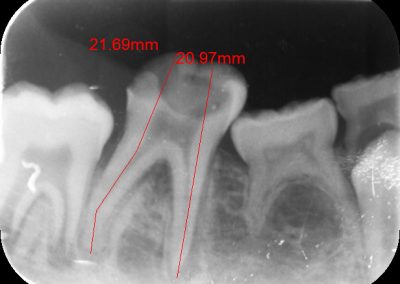

Files of different sizes are used to eliminate bacteria and infection and to shape the canals. The canals are disinfected thoroughly with irrigants and later the canals will be sealed in 3 dimensions with a special medicament called gutta-percha to prevent reinfection of the tooth and the access cavity will be sealed with a temporary filling.

After a few weeks, the tooth will be checked and when all the infection has cleared, a crown will be usually required to protect the restore the tooth to function.

Studies have shown thorough cleaning with instruments, disinfection and sealing the canals contribute to the successful healing of the infection and this success is reported as 95%.